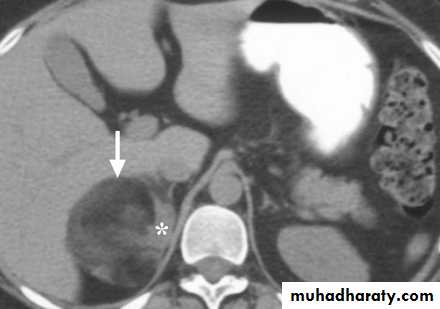

Localisation; abdominal CT or MRI.

CT scan of abdomen showing large left adrenal phaeochromocytoma. The normal right adrenal (white arrow) contrasts with the large heterogeneous phaeochromocytoma arising from the left adrenal gland (black arrows).